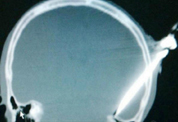

어느날 핑은 생산라인 앞에 앉아있던 치우의 뒤로 다가간 뒤, 칼로 그의 머리를 찔렀다. 핑이 손에 쥐고 있던 칼은 손잡이를 포함 약 8cm짜리였으며, 칼에 머리를 찔린 치우는 그대로 쓰러지고 말았다.

동료들은 치우가 당연히 죽었을 거라고 생각했다. 그러나 즉시 인근 병원으로 옮겨져 무사히 수술받은 치우는 현재 회복 중이다.

의료진은 “수술 중에도 출혈이 워낙 심해 걱정했다”며 “우리는 그가 평생 반신불수로 지내야 할 것으로 예상했다”고 말했다. 이어 “그러나 환자는 말하는 데만 다소 어려움을 겪을 뿐 그 외의 치료는 잘 진행되고 있다”고 덧붙였다. 의료진은 치우가 완전히 회복하기까지 몇 달 정도 걸릴 것으로 보고 있다.